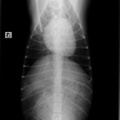

症例:【マルチーズMix 1歳齢 メス】

A:胸部レントゲン写真 正面像

B:胸部レントゲン写真 側面像

C:超音波画像 肺動脈領域の異常血流

D:左心系の拡張による二次的僧帽弁逆流

左側胸壁よりLevine 4/6の連続性心雑音が聴取された。胸部レントゲン検査において心拡大が認められ、超音波検査においても肺動脈領域に連続的な異常血流が観察された。大学病院を紹介受診され、手術が行われた。現在はACE阻害薬のみの内服で補助的治療を行っている。